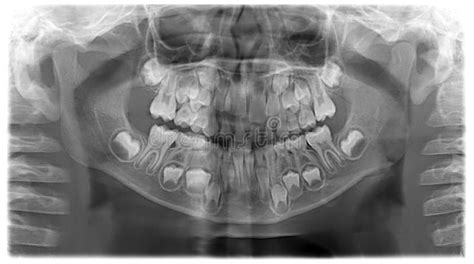

Si en esas primeras revisiones con el ortodoncista infantil se detecta algún problema, alteración en el alineamiento o mordida de los dientes, en función del caso y la edad del niño, será el especialista quien decidirá si empezar un tratamiento de ortodoncia infantil. Eso sí, todo esto a partir de los 6 años, a través de un estudio completo (radiografías y fotografías intraorales y extraorales) y un plan de tratamiento personalizado.

En nuestra clínica, puedes pedir cita directamente para valoración con el Ortodoncista y la primera visita y valoración no tendrán coste. Solicita la primera cita gratis para que nuestros especialistas puedan valorar que tratamiento es el más indicado para ti. Realización del estudio de Ortodoncia: El siguiente paso es realizar un estudio de Ortodoncia; para ello, será necesario tomar unos moldes de la boca, completar el registro fotográfico y hacer unas radiografías (panorámica y telerradiografía).La realización del estudio de Ortodoncia en A Coruña no tiene coste y es sin compromiso.

Realizaremos una exploración bucal y tomaremos unas fotografías de los dientes que luego os enseñaremos; esto nos ayuda a explicaros mejor vuestro caso. Si es necesario, haremos también unas radiografías digitales.

- ¿Cuándo se deben hacer las radiografías dentales en los niños? Las radiografías dentales en niños se realizan cuando es necesario evaluar áreas que no son visibles a simple vista, como los dientes en crecimiento y la estructura ósea.